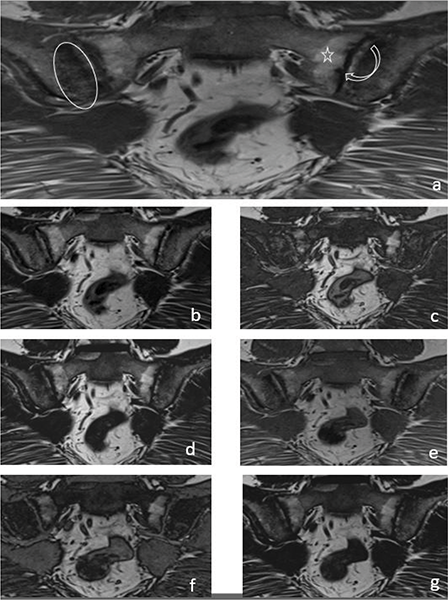

Figure 2

A 33‑year‑old female patient with iliac side sclerosis (ovoid circle), sacral side periarticular fat deposits (star) and iliac‑sacral facial erosions (curved arrow) in both sacroiliac joints marked on a T1W images (a). These findings can also be seen in T2W Dixon IP (b), T2W Dixon OP (c), T2W Dixon FO (d), T1W Dixon IP (e), T1W Dixon OP (f) and T1W Dixon FO (g) images.